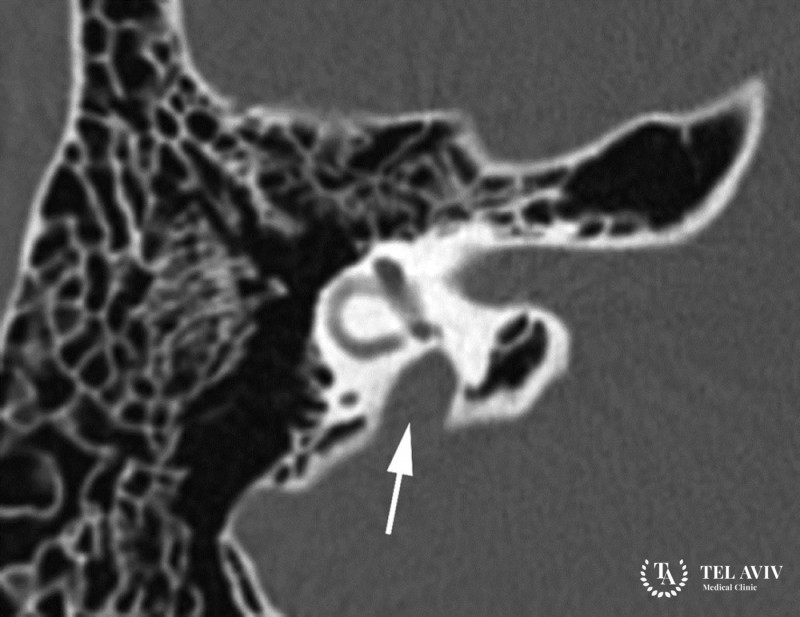

Для диагностики потенциально опасного заболевания применяют компьютерную томографию. Височные кости изучаются на специальном аппарате, врач визуализирует патологический процесс.

Повышенное давление в перилимфе внутреннего уха приводит к постепенному формированию патологии. Врожденные аномальные нарушения становятся причиной Gusher-синдрома. Распространенный предрасполагающий фактор – отсутствие костных стен между базальными улиточными завитками и днищем в внутреннем слуховом проходе.

Базальный улиточный завиток – фистулы, разделяющие субарахноидальное пространство мозга, периферическое, лимфатическое пространство во внутреннем ухе.